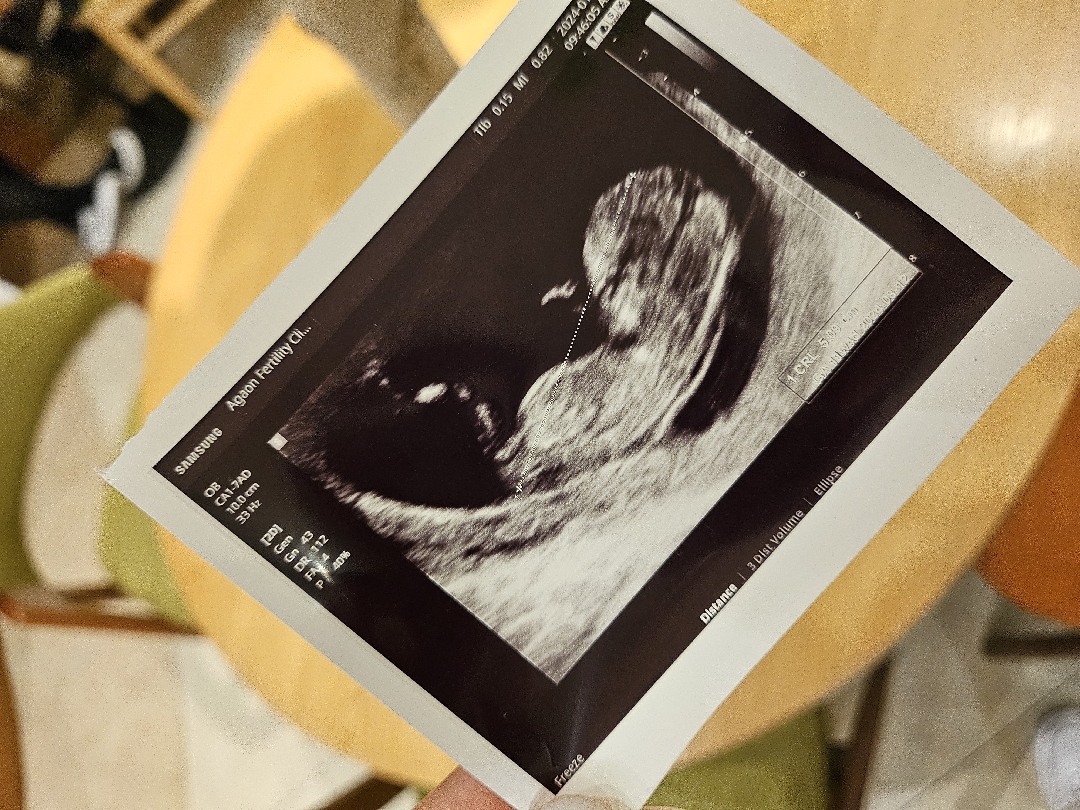

각도법봐주실수잇나요~~?

친구들이 딸이라고 하는데 ㅎㅎ 다른분들의견도궁금해요

딸 같아요ㅎㅎ

딸같네요

딸같아요!